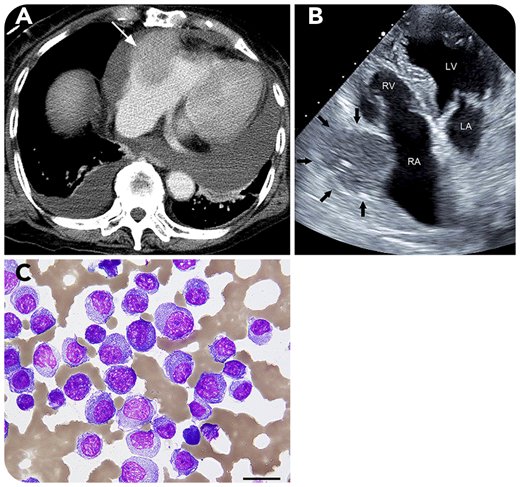

A 79-year-old woman visited our hospital because of back pain. Laboratory examination showed monoclonal λ light chains in the serum, and a population of 60% CD138+ plasma cells was found on bone marrow biopsy. Karyotype was normal, and whole-body computed tomography (CT) found no extramedullary lesions. She was diagnosed with immunoglobulin A λ-type multiple myeloma (MM), classified as stage 2 according to the Revised International Staging System; she started treatment with bortezomib plus dexamethasone and achieved complete response. One year later, multiple tumors in her right mammary gland were detected on CT. Mammary gland biopsy found plasmacytoma, resulting in a diagnosis of extramedullary lesions in MM. Four years after first visit, she was admitted with heart failure. Contrast-enhanced CT (panel A) and echocardiography (panel B; LA, left atrium; LV, left ventricle; RA, right atrium; RV, right ventricle) revealed a moderate amount of pericardial effusion and a mass (3.8 × 4.5 cm) in the right atrial wall (white arrow in panel A and black arrows in panel B) consistent with cardiac tamponade; pericardial drainage was then performed. Cytology for the bloody pericardial effusion showed clusters of plasma cells (panel C; periodic acid Schiff stain; original magnification ×400), indicating an extramedullary lesion to the pericardium. Fluorescence in situ hybridization from the bone marrow detected no cytogenetic abnormality. Although daratumumab, carfilzomib, and pomalidomide were administered, the mass enlarged, and she died thereafter.